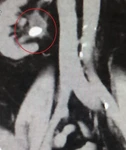

Resim 2. Koronal kesitli BT'de sağ börekteki taş görülmekte.

Çekilen bel MR’ında sağ böbrek pelvisinde üreter girişinde 1.5 cm çapında böbrek taşı tespit edildi.